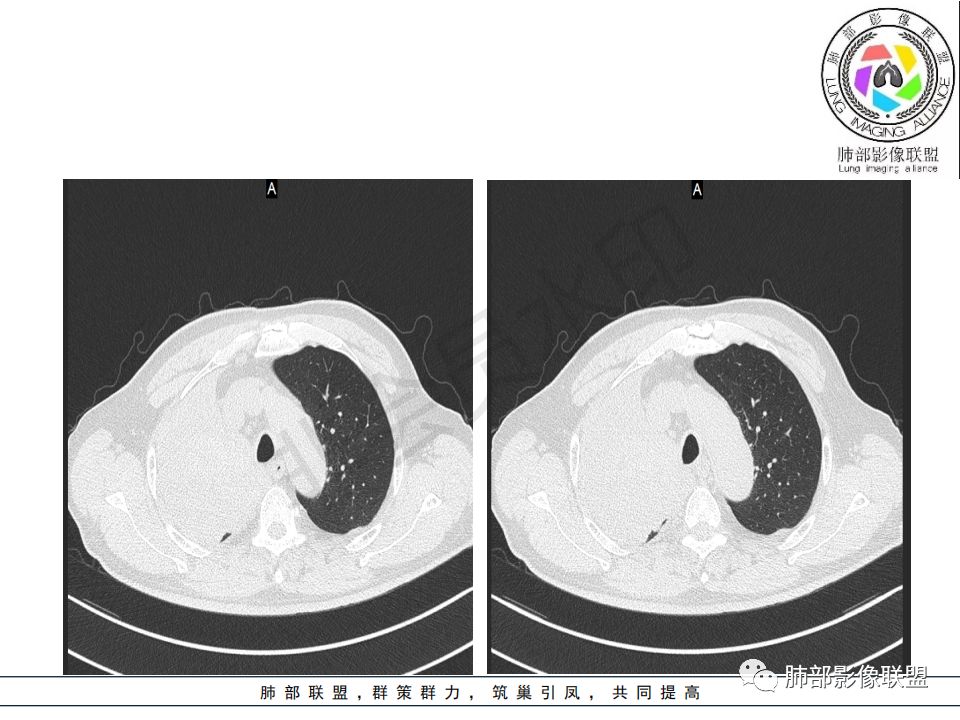

病史:男.77岁,咳嗽1月;干咳,少许白痰,无发热,2013胃癌术后,角蛋白24.65(0-3.07),SCC和proGRP不高;

影像:影像右侧大支气管阻塞,临床没有症状或很轻微,要想到胃腺癌转移;胸壁代偿好,透亮度稍低不明显,慢性过程;34.8-52.5HU,主病灶支气管前壁另有1结节,都做成增强两期了,动脉期较平扫有强化;

诊断:多发,转移,无淋巴结及胸腔积液;

鉴别:原发鳞癌。

晨读:患者老年男性,以咳嗽一月就诊,少量白痰,胸CT:纵隔右移,右肺体积缩小,气管下段管壁可见结节样改变,气管软骨变形,气管下段及右主支气管可见新生物向管壁浸润,并向管腔外生长,右上肺肺不张,但不张边缘可见病灶呈膨胀性生长,可见分叶,增强后强化明显。考虑:肺部恶性病变(鳞癌?)

右肺上叶肿块,边缘光滑,略膨隆,近段支气管堵塞,平扫密度均匀,增强后不均匀强化,其内可见不规则血管和坏死,纵隔淋巴结肿大,老年男性,无感染性病史,综合考虑恶性肿瘤(鳞癌,腺癌),鉴别:OP(一般下叶多见)

老年男性,右肺气管内软组织影,支气管变窄截断,右肺上叶阻塞性肺不张,内见细点状钙化,周围看见小结节,增强不均匀强化,考虑:原发肺恶性鳞癌。胃癌病史,转移不出外。鉴别神经内分泌癌,类癌。

晨读病例:老年男性,症状轻,右侧胸廓略塌陷,右肺主支气管内外软组织影,支气管变窄截断,右肺上叶不张,其内见细砂样钙化,周围看见小结节,右肺门看见一淋巴结稍大,增强不均匀强化,胃癌病史,常规考虑:转移,或原发肺恶性鳞癌。鉴别支气管TB?